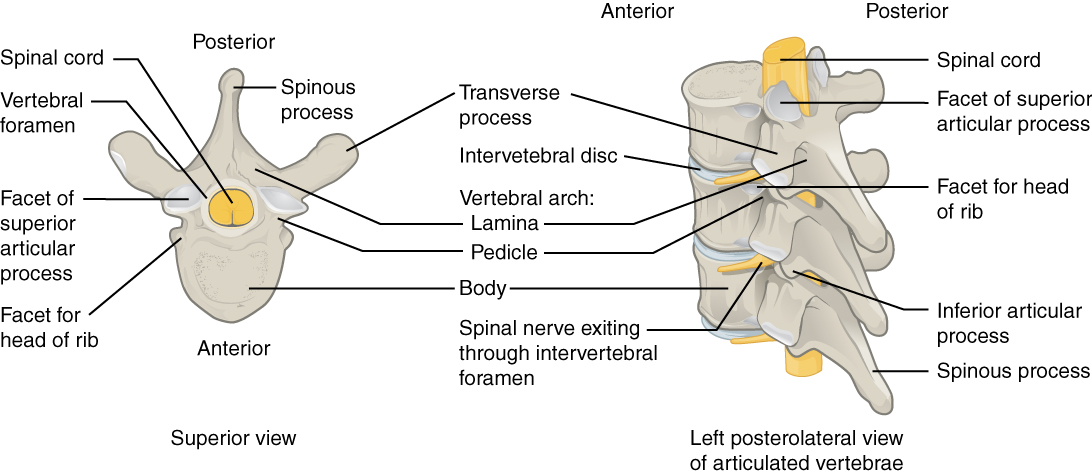

Https www alamy de bulletin der naturlichen histort museum geologie serie s andrews und y fernandez jalvo abb 16 a menschliche achse wirbel m 54042 zeigt die konformation des cut markierungen entlang der vorderen oberflache dies ist der bereich der befestigung der vorderen langsband und daruber hinaus die superior markierungen sind wahrscheinlich auf die ablosung der achse von der atlas und die hinteren markierungen aus um die loslosung der achse von der dritten halswirbel x 12 b schematische zeichnung des menschlichen schadel und oberen wirbel angezeigt um die disposition der beiden muskeln die an der inneren oberflache o image233869895 html (Dateityp jpg)

Bulletin Der Naturlichen Histort Museum Geologie Serie S Andrews Und Y Fernandez Jalvo Abb 16 A Menschliche Achse Wirbel M 54042 Zeigt Die Konformation Des Cut Markierungen Entlang Der Vorderen Oberflache